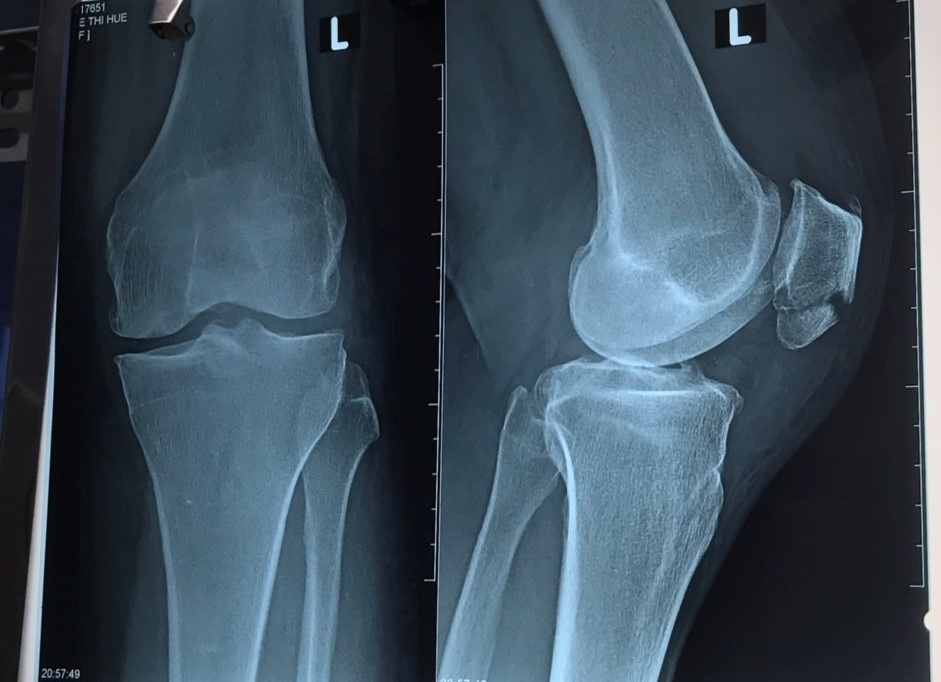

Bệnh nhân nhập viện trong trạng thái tỉnh táo, tiếp xúc tốt, thể trạng trung bình, niêm mạc hồng, huyết áp cao. Qua khám cận lâm sàng, bệnh nhân được chẩn đoán gãy xương bánh chè trái. Do đường huyết, huyết áp cao nên được điều trị nội khoa để hạ đường huyết và huyết áp.

Đến 9h35 phút ngày 21/12, khi đường huyết và huyết áp dần ổn định, người bệnh được chuyển lên phòng mổ với chẩn đoán gãy kín xương bánh chè. Dự kiến mổ kết hợp xương bánh chè trái.

Hình ảnh chụp X-quang khớp gối trái của người bệnh. Ảnh: BVCC.